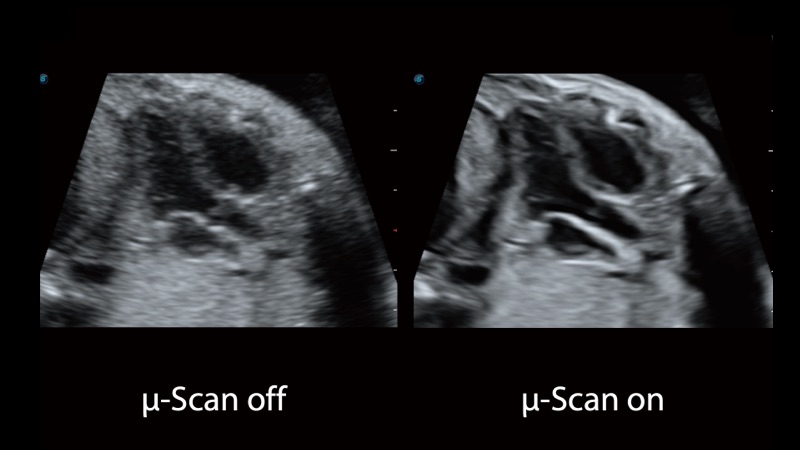

開立醫(yī)療通過不斷的技術(shù)創(chuàng)新,為大眾的生命健康提供持續(xù)關(guān)愛。P12 Plus采用全新一代超聲成像平臺,新平臺旨在將真實還原組織解剖結(jié)構(gòu)作為首要目標(biāo)。平臺采用全新集成化硬件模塊,搭載新一代芯片,系統(tǒng)性能得到大幅提升,為您的診斷提供了豐富的臨床信息。優(yōu)異的圖像表現(xiàn),豐富的探頭配置,全面的應(yīng)用功能,為您日常診斷提供了可靠的助手。

彩色多普勒超聲診斷系統(tǒng)